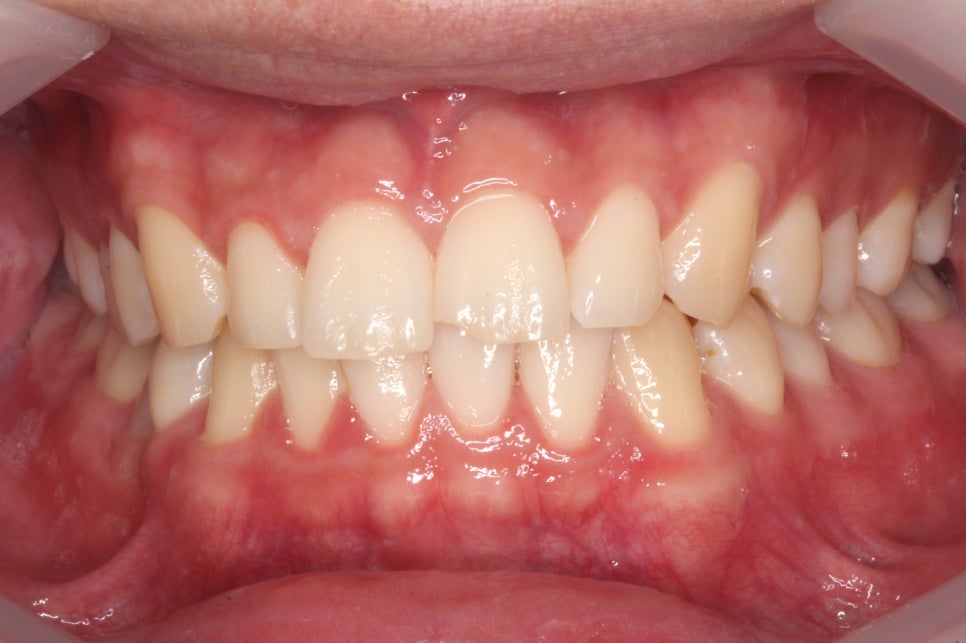

□ 앞니 마모

출처:투디 치과/ 앞니 마모 사례의 블링스 전후 사진입니다.

앞니가 마모되어 빈 공간이 많이 보이는

전 사진이 블링스를 만난 후 빈틈없이 자연스럽게

개선된 모습을 볼 수 있습니다.